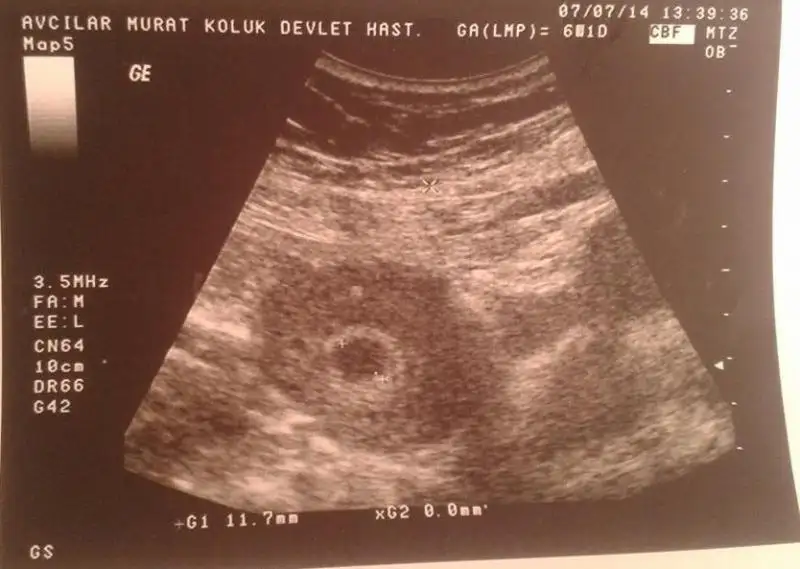

slm kullandığım jelden önce pembe leke,dr.verdiği progegestron iğnesinden sonra kahverengiye döndü neyseki dr. sorun yok dedi yarın keseyi görmeye gitcem çok heyecanlıyım